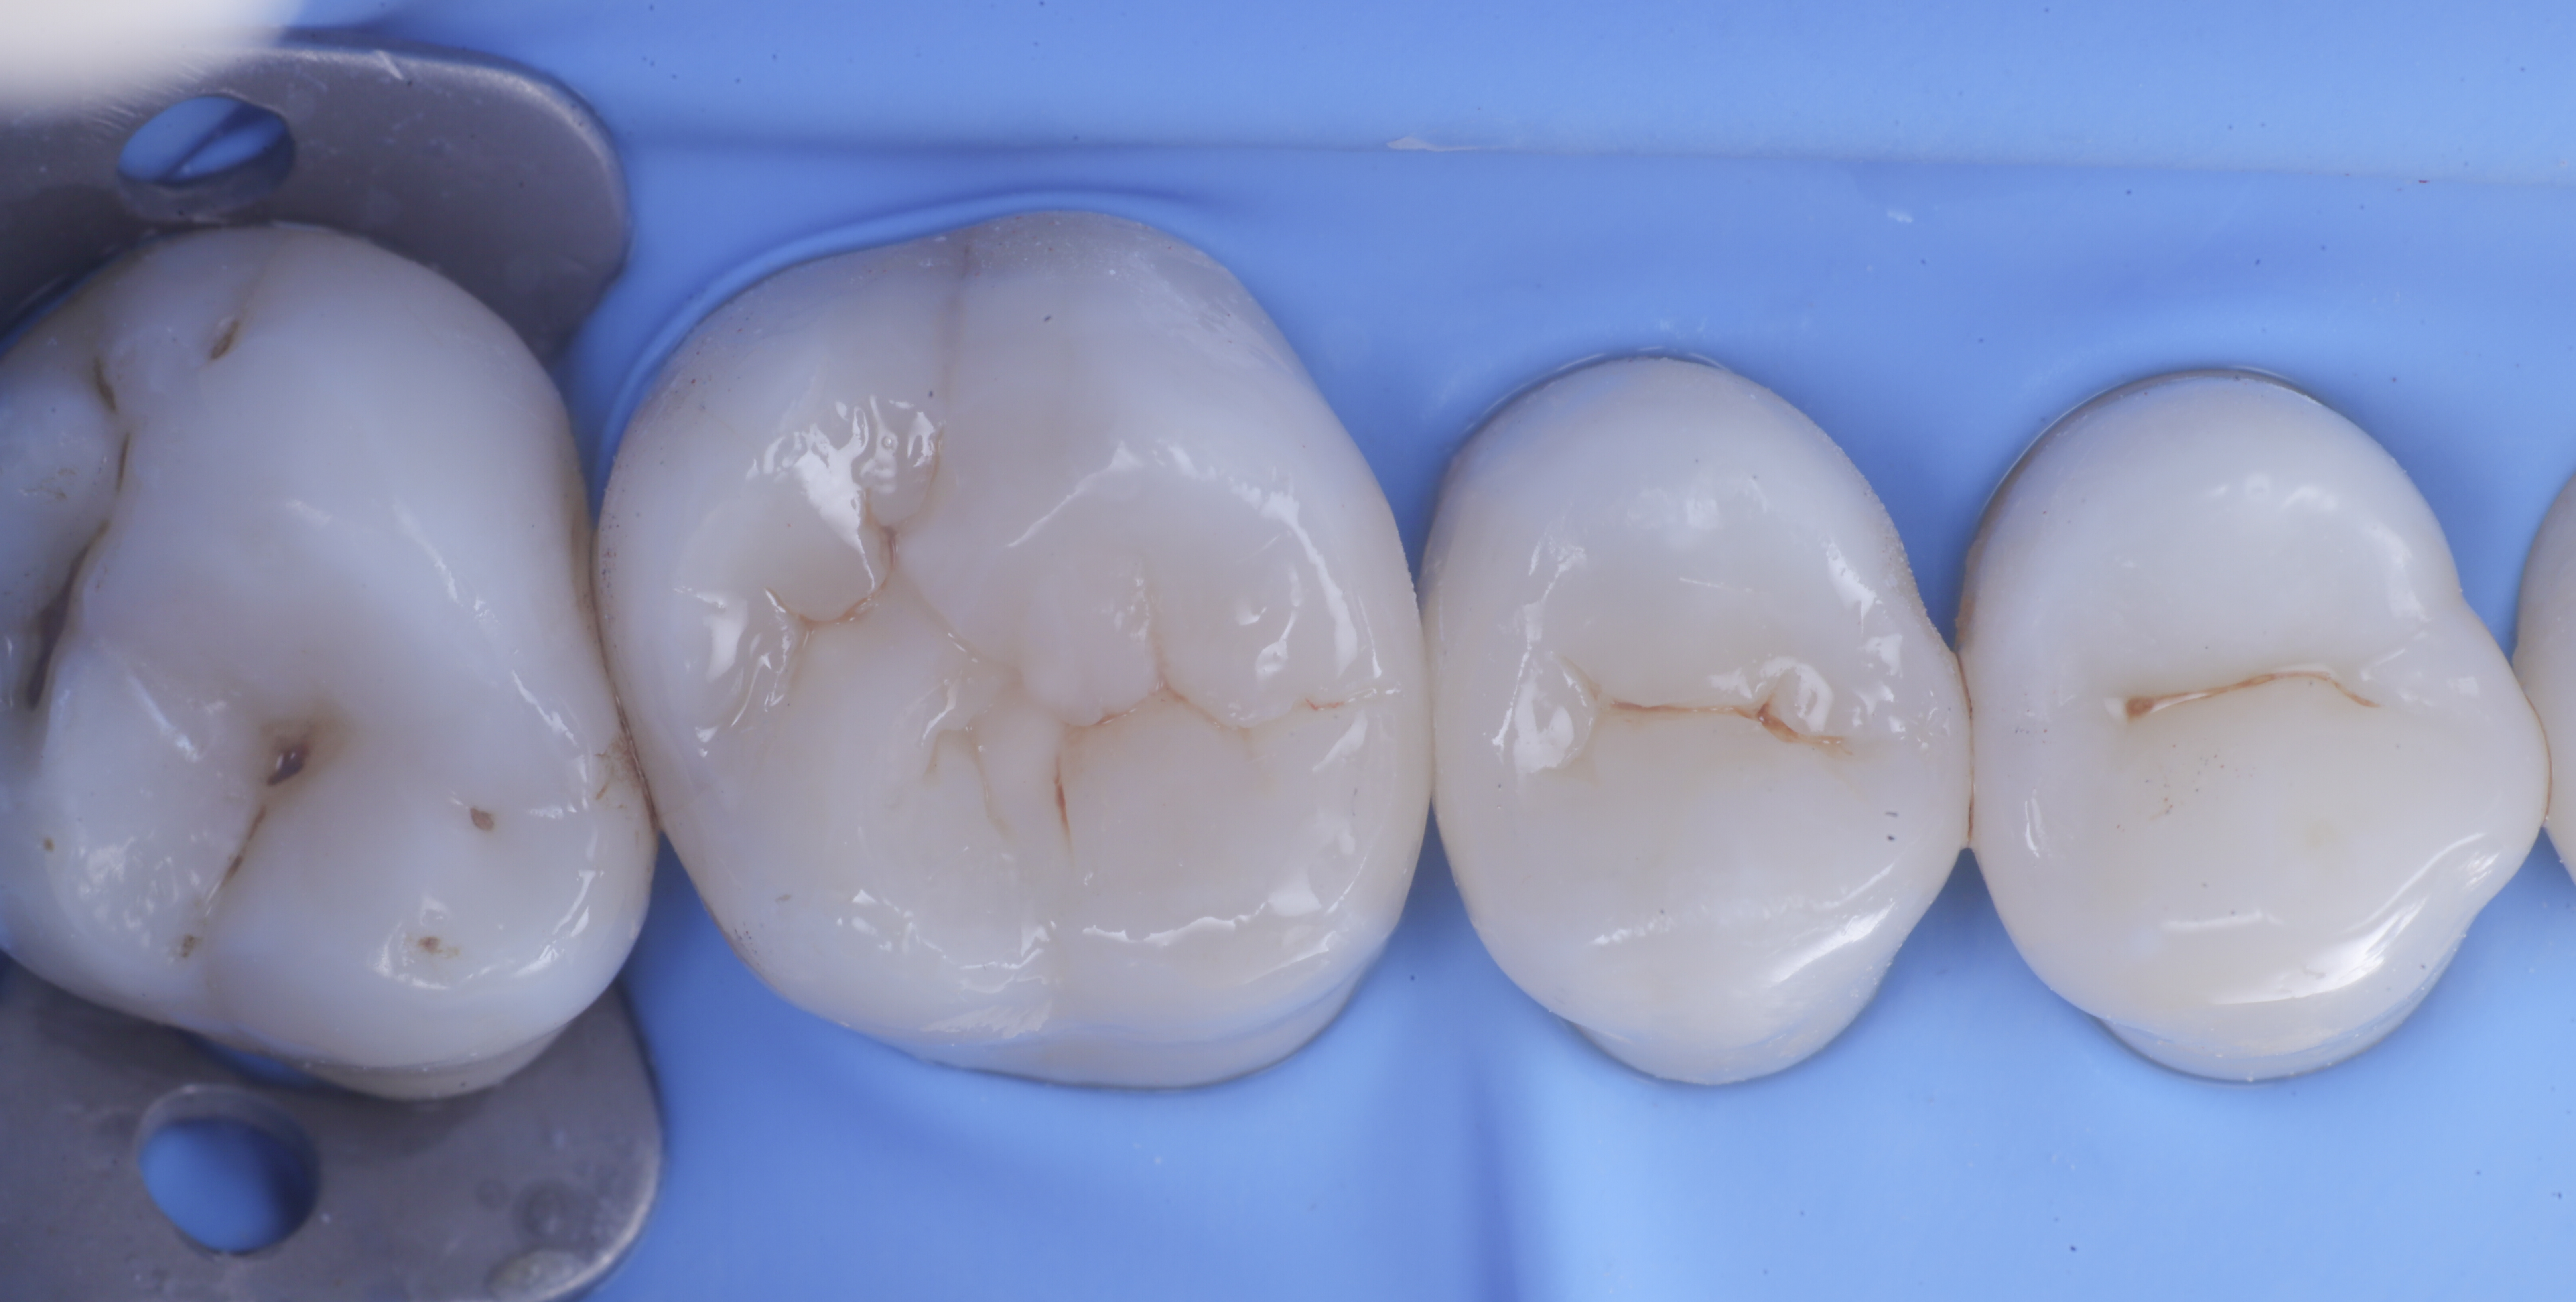

foto 1 Fotografia iniziale

foto 2 Isolamento e aspetto delle cavità ultimate